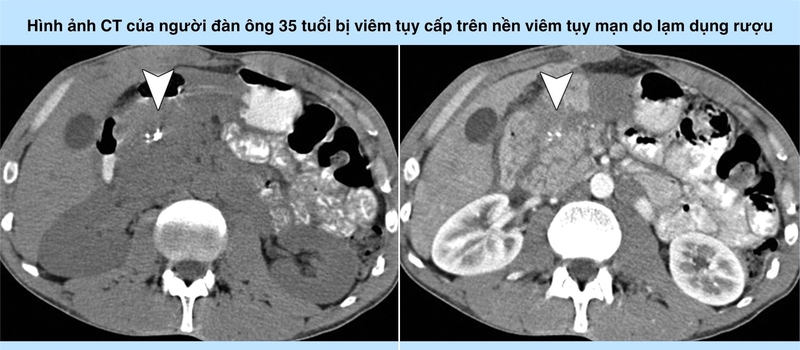

Hình ảnh CT của một người đàn ông 35 tuổi bị viêm tụy cấp tính trên nền mạn tính do lạm dụng rượu

Ở hình bên trái, hình ảnh CT pha đối chứng cho thấy một số vôi hóa ở đầu tụy (mũi tên) gợi ý viêm tụy mãn tính.

Ở hình bên phải, hình ảnh CT tăng cường độ tương phản (giai đoạn nhu mô tụy) cho thấy sự tăng cường không đồng nhất của tụy, và đầu tụy có vẻ phù nề với sự kết dính của mỡ quanh tụy. Có các tập hợp dịch quanh tụy nhỏ (tập hợp dịch tụy cấp tính) (mũi tên).